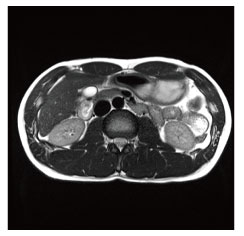

MRI(Magnetic Resonance Imaging:磁気共鳴画像診断装置)検査は、強力な磁石でできた円筒状の機械に入り、磁気や電波の力を利用して体の断面や血管を撮影する検査です。

当院のMRI画像集